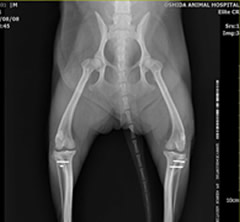

膝蓋骨内方脱臼

両側性の膝蓋骨内方脱臼により持続した跛行がありました。しかし、飼い主様は足の異常に気づいておらず、ワクチン接種時に判明しそのまま手術となりました。小型犬に多いトラブルですので、獣医師に触診してもらうだけでもおおよその異常は見つけられるハズです。